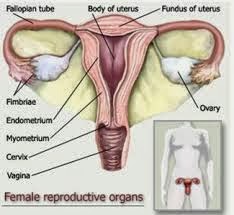

4+ Fungsi Ovarium Pada Wanita (Gambar Lengkap) - Ilmusiana

4+ Fungsi Ovarium Pada Wanita (Gambar Lengkap) - Ilmusiana